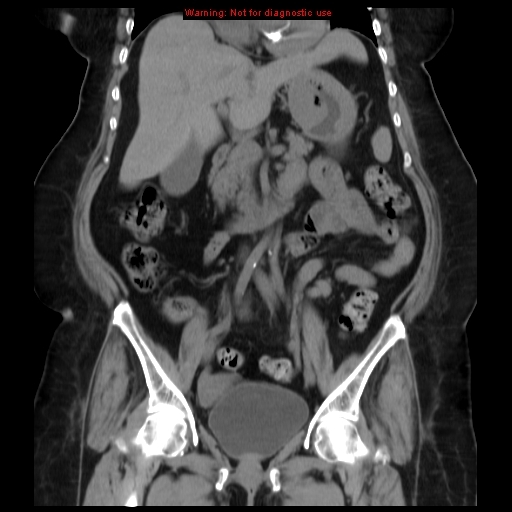

CT of the abdomen demonstrates a mass arising from the greater curvature of the body of the stomach. It is centrally ulcerated with locules of gas and contrast seen within it, but without evidence of perforation. It is a focal abnormality with thick heaped-up shoulders.

At the splenic hilum there appears to be an enlarged lymph node (this should be confirmed on thin slice and coronal reformats). No convincing evidence of metastatic disease.

The left kidney is atrophic and contains a number of what appear to be hyperdense cysts (which should be confirmed on ultrasound). The right kidney has a large simple cyst.

This patient went on to have a total gastrectomy after the stomach tumour was identified on gastroscopy.